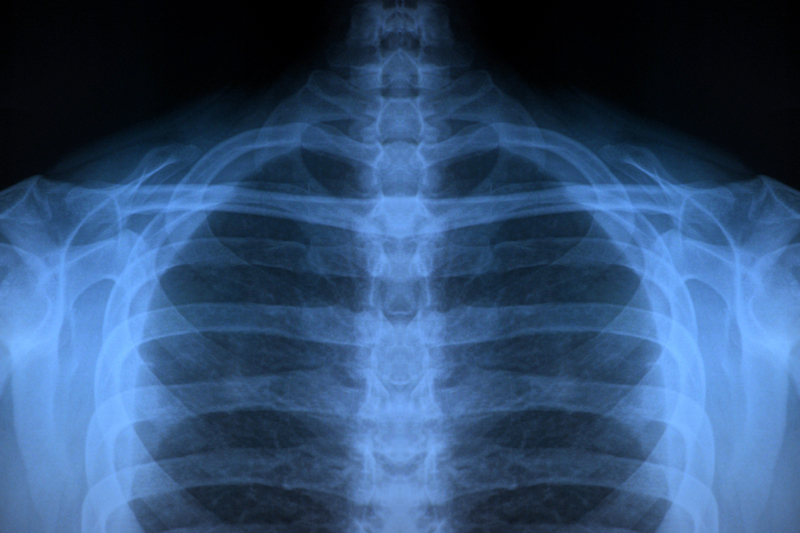

Radiografii false făcute de AI atât de bine încât au păcălit atât radiologi, cât și instrumentul care le-a creat. Cercetătorii trag un semnal de alarmă

Radiografiile false, generate de inteligența artificială (AI) astfel încât să semene cu rezultate reale provenite de la pacienți umani, pot păcăli atât radiologi cu experiență, cât și instrumentele AI în sine, conform unui studiu la care au luat parte 17 radiologi din 12 spitale aflate în șase țări, a scris Reuters.

Cei 17 radiologi au primit 264 de radiografii, dintre care jumătate fuseseră create de instrumente de AI ca ChatGpt sau RoentGen.

Când radiologii nu cunoșteau adevăratul scop al studiului, doar 41% dintre ei au identificat spontan imagini generate de AI, arată raportul publicat în revista Radiology.

Când au fost informați că în setul de date sunt și imagini sintetice, precizia medie a radiologilor în diferențierea imaginilor reale de cele sintetice a crescut la 75%.

Faptul că există radiografii deepfake suficient de realiste pentru a-i înșela pe radiologi „creează o vulnerabilitate cu mize mari pentru litigii frauduloase dacă, de exemplu, o fractură fabricată ar putea fi imposibil de distins de una reală”, a avertizat coordonatorul studiului, Dr. Mickael Tordjman de la Școala de Medicină Icahn de la Mount Sinai din New York, într-un comunicat.

El a atras atenția că „există, de asemenea, un risc semnificativ de securitate cibernetică în cazul în care hackerii ar obține acces la rețeaua unui spital și ar injecta imagini sintetice pentru a manipula diagnosticele pacienților sau ar provoca haos clinic pe scară largă prin subminarea fiabilității fundamentale a dosarului medical digital”.

Patru modele lingvistice mari, GPT-4o și GPT-5 de la OpenAI, Gemini 2.5 Pro de la Google și Llama 4 Maverick Meta, au detectat imaginile false cu o precizie care a variat între 57% și 85%.

Nu a fost detectate toate nici măcar de instrumentul cu care au fost generate

Nici măcar ChatGPT-4o, modelul care a creat radiografiile false, nu a reușit să le depisteze pe toate, chiar dacă a identificat mai multe decât celelalte instrumente, spun cercetătorii.

Aceștia consideră că s-ar putea impune crearea unor eventuale garanții digitale pentru a ajuta la distingerea imaginilor reale de cele false și pentru a preveni manipularea.

„Poate că vedem doar vârful aisbergului”, a declarat Tordjman despre posibilitatea unor scanări CT și RMN false. „Acum este esențială stabilirea unor seturi de date educaționale și a unor instrumente de detectare”, a conchis el.